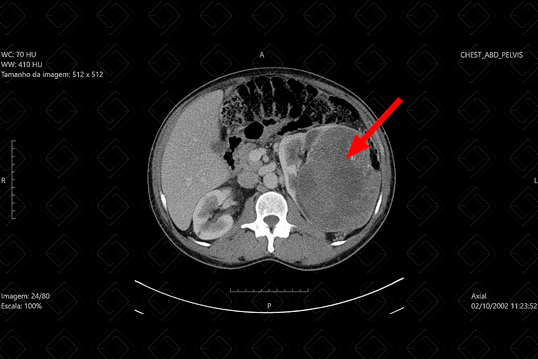

Descrição da figura: Tomografia computadorizada do abdome após injeção do contraste, na fase nefrográfica, evidenciando volumosa lesão renal esquerda, parcialmente exofítica, com densidade de partes moles, heterogênea, contendo áreas internas hipocaptantes do meio de contraste (seta vermelha). Seu resultado final foi compatível com carcinoma de células renais (CCR).

• Carcinoma de células renais (CCR): Em boa parte dos casos são achados de imagem, porque os sintomas ocorrem mais tardiamente. Seu pico de incidência é em torno dos 60-70 anos. Seus principais subtipos incluem: carcinoma de células claras (mais comum subtipo neste grupo. Em geral, são lesões hipervasculares e heterogêneas nos estudos de imagem, por necrose, sangramento ou degeneração cística), carcinoma papilífero (segundo subtipo mais comum, comumente são hipovasculares e homogêneas) , carcinoma cromófobo (melhor prognóstico, com achados de imagem inespecíficos, sendo importante diagnóstico diferencial com oncocitoma);